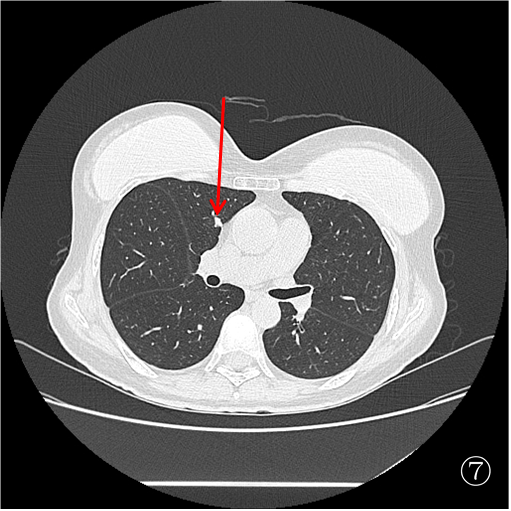

为进一步明确诊断,制定后续治疗方案,杨志祥主任组织讨论后拟行 CT 引导下肺占位穿刺活检,由于右肺占位(图①)毗邻升主动脉及肺动脉,初步拟定行图②左肺占位穿刺活检。

患者俯卧定位扫描(图③):由于胸腔及肺组织受压,左肺占位距离膈肌<1 cm,行穿刺活检必然损伤膈肌,可能造成严重并发症。于是决定经胸前穿刺右肺占位活检(图④),但由于病灶小于 1 cm 且邻近大血管,必须精准制导(图⑤)。穿刺后扫描局部少许出血,未见气胸(⑥)。